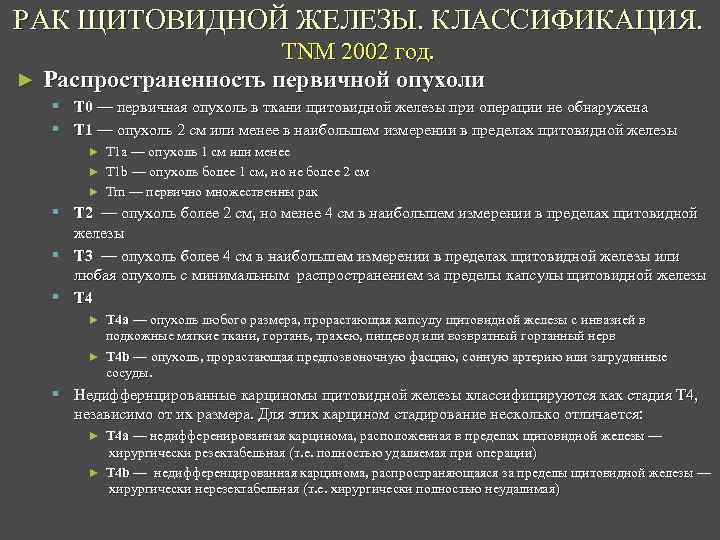

РАК ЩИТОВИДНОЙ ЖЕЛЕЗЫ. КЛАССИФИКАЦИЯ. TNM 2002 год. ► Распространенность первичной опухоли § T 0 — первичная опухоль в ткани щитовидной железы при операции не обнаружена § T 1 — опухоль 2 см или менее в наибольшем измерении в пределах щитовидной железы ► T 1 a — опухоль 1 см или менее ► Т 1 b — опухоль более 1 см, но не более 2 см ► Tm — первично множественны рак § T 2 — опухоль более 2 см, но менее 4 см в наибольшем измерении в пределах щитовидной железы § T 3 — опухоль более 4 см в наибольшем измерении в пределах щитовидной железы или любая опухоль с минимальным распространением за пределы капсулы щитовидной железы § T 4 ► T 4 a — опухоль любого размера, прорастающая капсулу щитовидной железы с инвазией в подкожные мягкие ткани, гортань, трахею, пищевод или возвратный гортанный нерв ► T 4 b — опухоль, прорастающая предпозвоночную фасцию, сонную артерию или загрудинные сосуды. § Недиффернцированные карциномы щитовидной железы классифицируются как стадия T 4, независимо от их размера. Для этих карцином стадирование несколько отличается: ► T 4 a — недифференированная карцинома, расположенная в пределах щитовидной железы — хирургически резектабельная (т. е. полностью удаляемая при операции) ► T 4 b — недифференцированная карцинома, распространяющаяся за пределы щитовидной железы — хирургически нерезектабельная (т. е. хирургически полностью неудалимая)